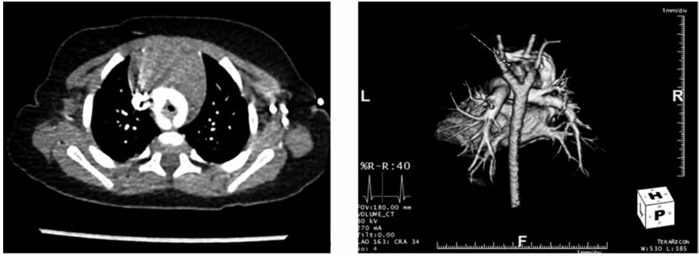

Mãe de lactente de um ano refere que seu filho apresenta chiado no peito desce o nascimento. Vem sendo tratado como bronquiolite desde então. Procurou novo pediatra que o encaminhou ao cardiopediatra. Mãe apesar de desconfiada passou em consulta e realizou radiografia de tórax normal, eletrocardiograma normal, ecocardiograma que viu alguma alteração na aorta nada conclusivo e angiotomografia e tomografia de tórax.

Enunciado 3561515-1

Com base nessas ilustrações, qual seu diagnóstico?